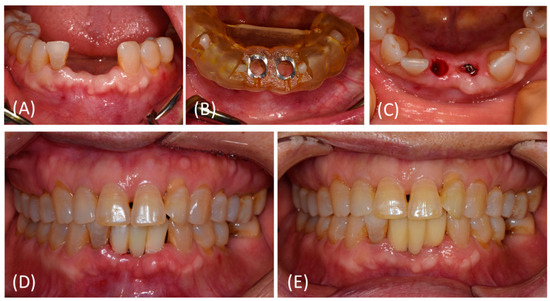

2.3. Treatment Procedures

2.3.1. Virtual Planning, 3D Surgical Templates, Provisional prostheses

2.3.2. Surgical Procedure

2.3.3. Prosthetic Procedure